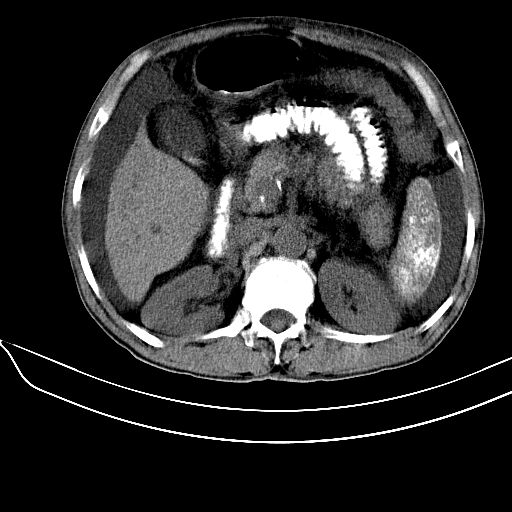

肝硬化明确,同意11楼是否做pse了。不然该考虑血液系统疾病了。血吸虫暂不考虑,1,肝肠无明显钙化。2,钙化形态该为条片状。

64岁血管壁钙化也要考虑血吸虫吗?肝硬化肯定。这种脾钙化很像介入术后改变。没见过血吸虫性肝硬化啥样?

长期肝硬化导致的淤血性脾内钙化,超声杂志见过报道.

脾脏钙化多由炎症或结核引起,寄生虫卵或钙质沉积亦可导致,等等。